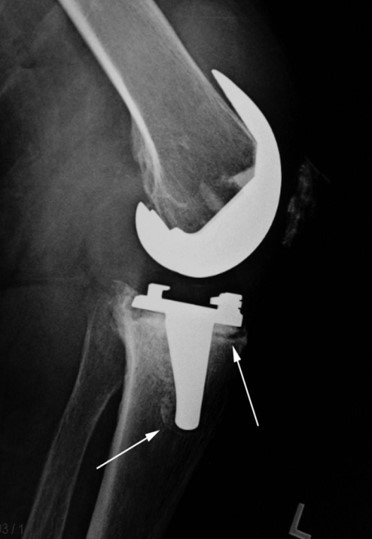

Приклад 3. Хвора К. 52 років. Діагноз: Деформівний IVст. гонартроз, стан після ТЕП лівого КС (2013р.). ІМТ хворої складає 35 балів. Асептична нестабільність компонентів ендопротеза лівого колінного суглоба, міграція великогомілкового компоненту (2017 р.) (рис. 2 а). Хворій виконано ревізійне ендопротезування: видалення компонентів ендопротезу, виявлений дефект медіального виростку великогомілкової кістки тип Т3А за класифікацією АОRI [G.A. Engh, C.H. Rorabeck, 1997]. Під час операції виконана кісткова пластика дефекту. Використаний ендопротез колінного суглоба з подовжувачами.